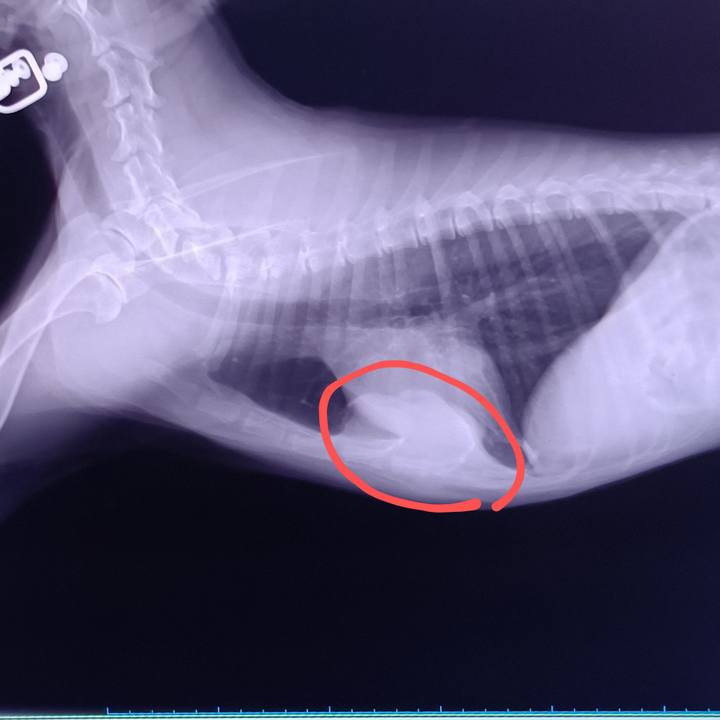

6/13レントゲン画像 触った感じは15mmくらいの膨らみが内部では広範囲に浸潤